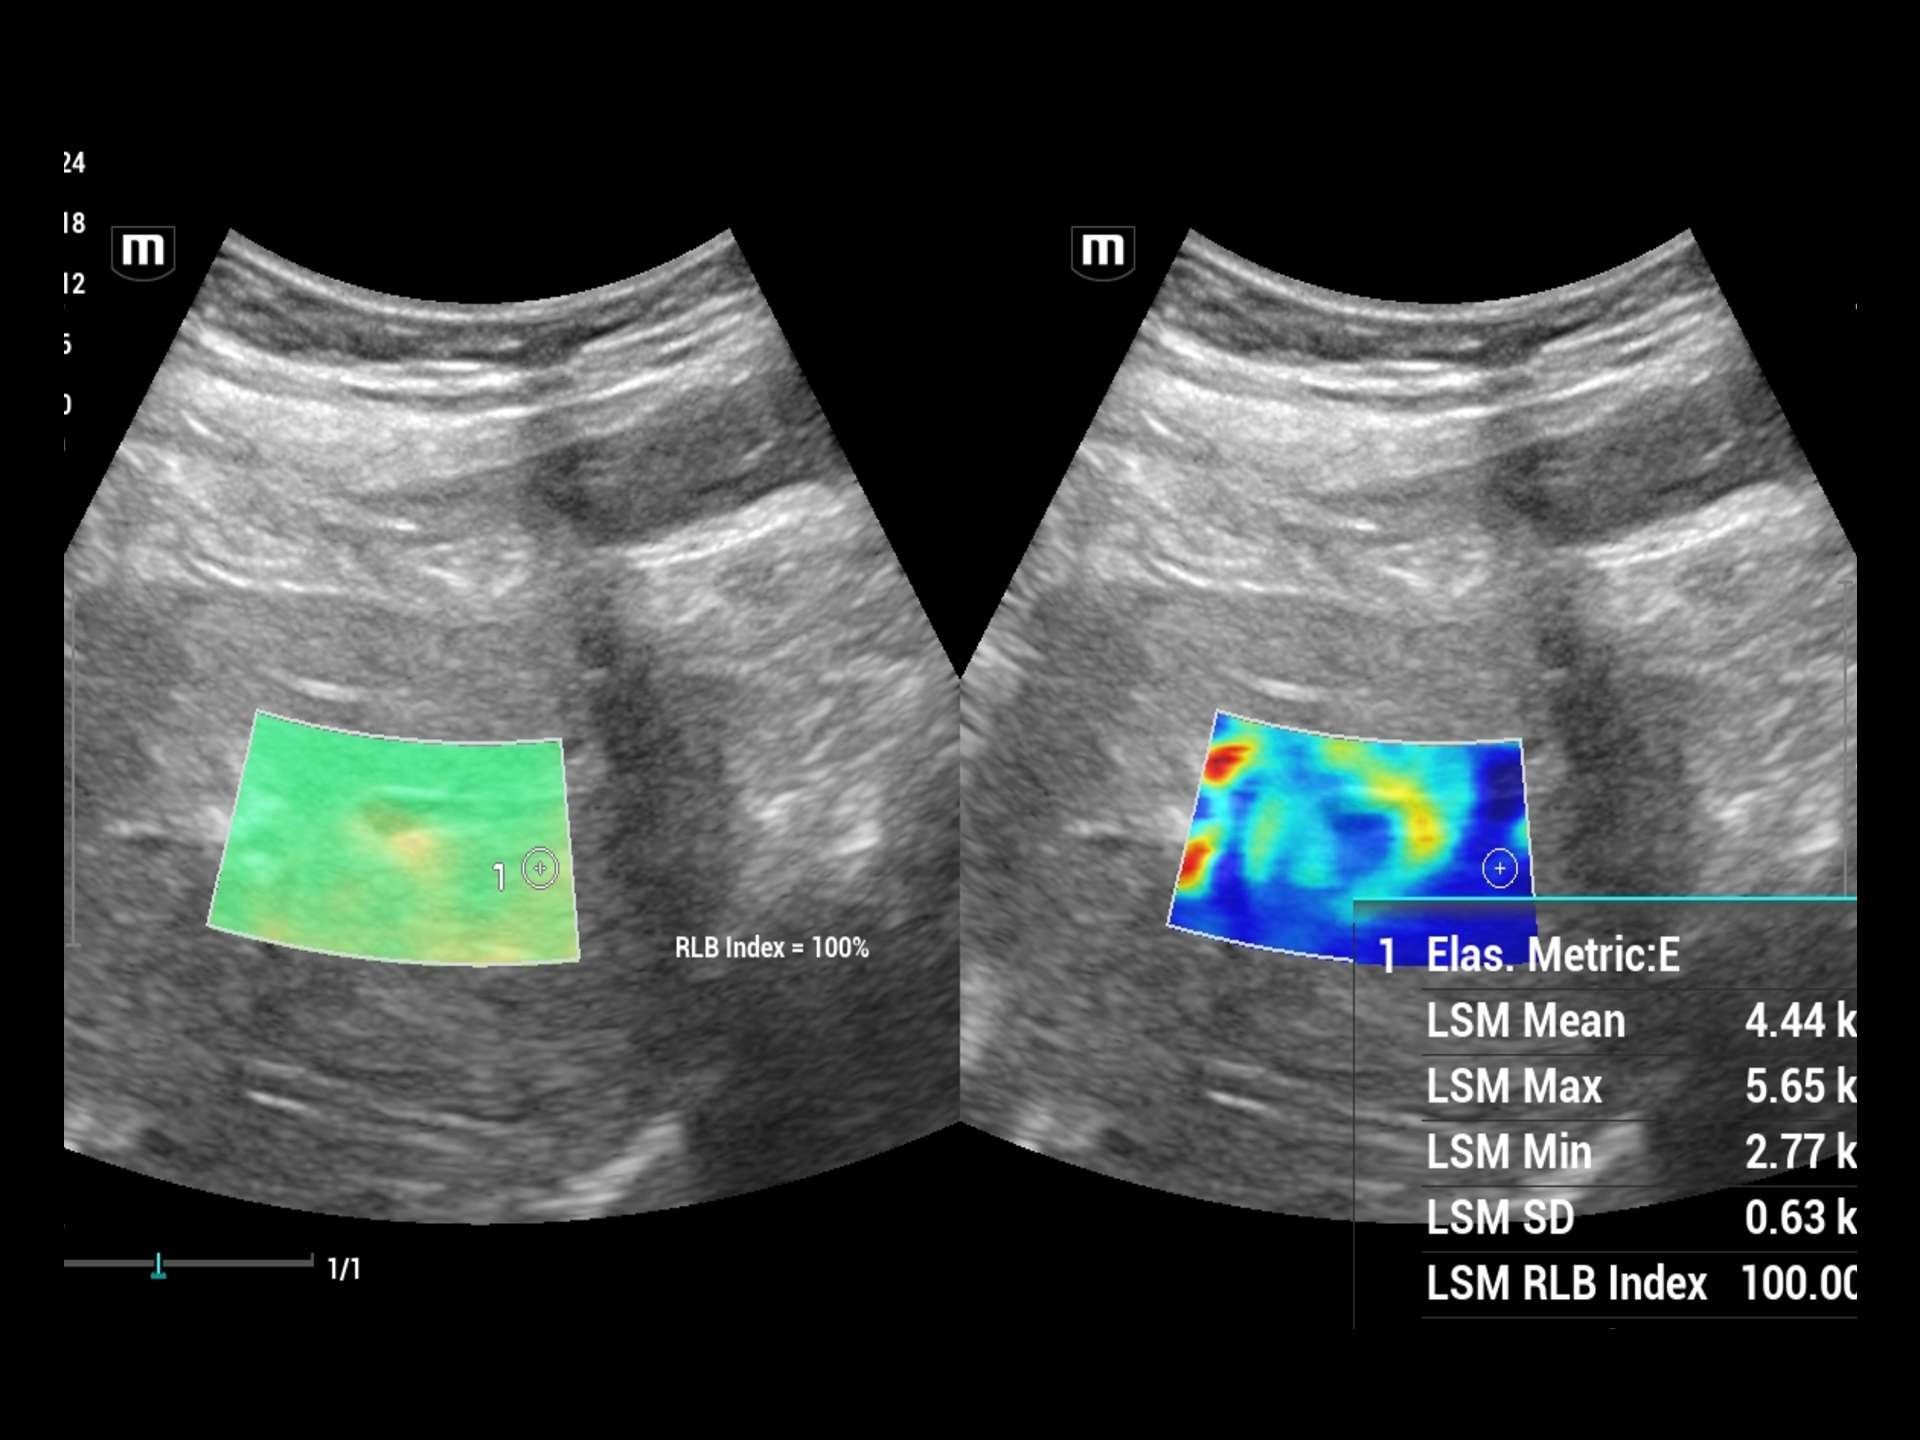

• Best in class Elastography (Fibroscan) scans are done for Breast, Liver and Prostate pathologies.